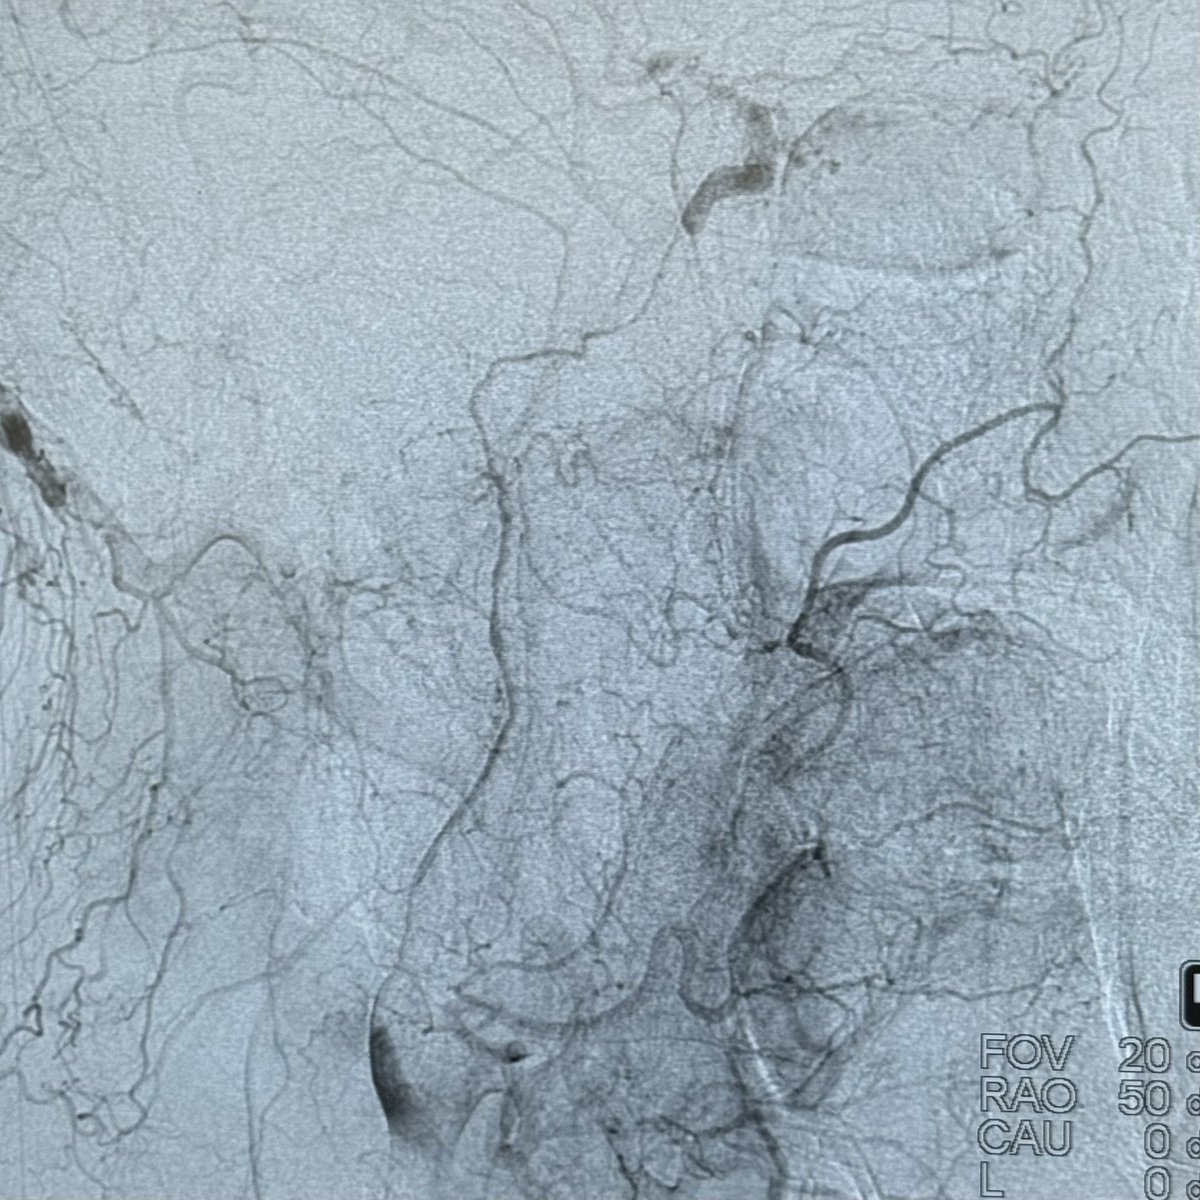

The Patient presented with recurrent episodes of loss of consciousness, DSA revealed extremely severe stenosis of the basilar artery. Under local anesthesia, a self-expanding drug-eluting stent was implanted via the radial approach. Postoperatively, the BA exhibited mild residual stenosis, and the patient's overall condition was satisfactory.

Long-term follow-up results are eagerly anticipated.

@daigaole Great case!

Do you continue with antiacoagulation or antiagregation?